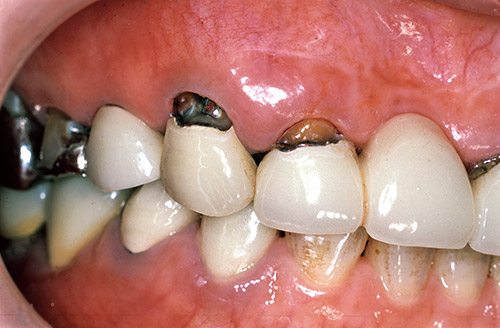

図12 右側前歯のメタルボンド修復歯の歯頸部根面露出とう蝕の症例。

図13 通法に従って窩洞形成。

図14 K‑エッチャントにより2、3秒処理の後、トライエスボンドNDとポーセレンボンドアクチベーターの混和物によりボンディング処理。